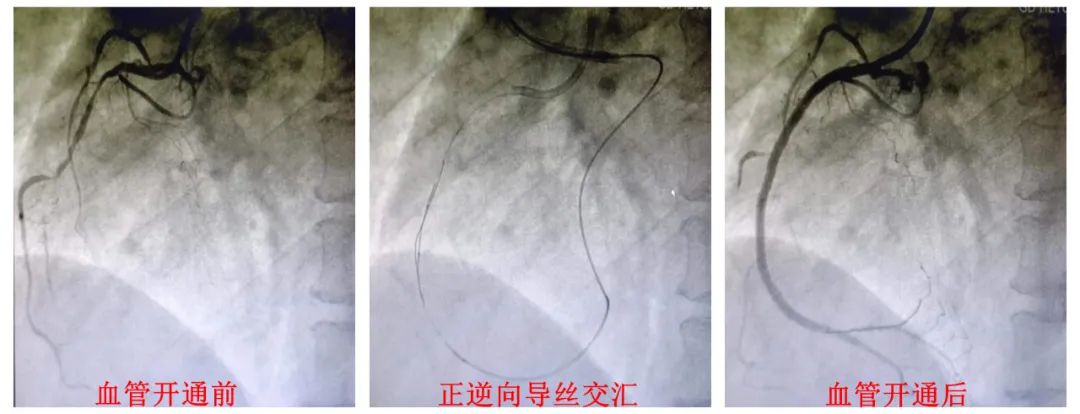

近日,我院心血管内科介入团队以日间手术方式成功为一名复杂CTO病变患者顺利开通血管。

为了给患者营造良好的就诊体验,缩短住院时间,决定按照日间手术方式进行。在心血管内科医护团队的精心安排下,患者入院当天下午即安排手术。何鹏程院长带领心内科介入团队克服术中种种困难,历时3小时,通过正逆向结合技术成功开通闭塞血管,术后患者恢复良好,48小时内办理出院。